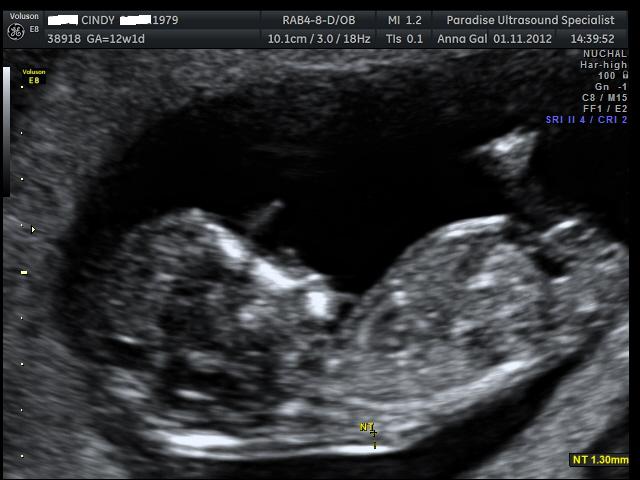

Here are the pics from my NT scan, the tech had a guess she said she is 70% positive the sex is.... can you guess? UPDATE - It's a boy :)